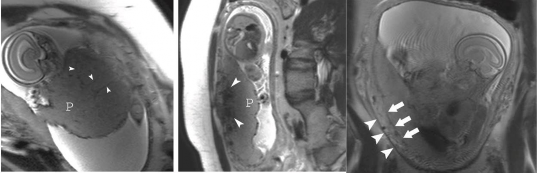

Hình 1.5: MRI rau cài răng lược [32]